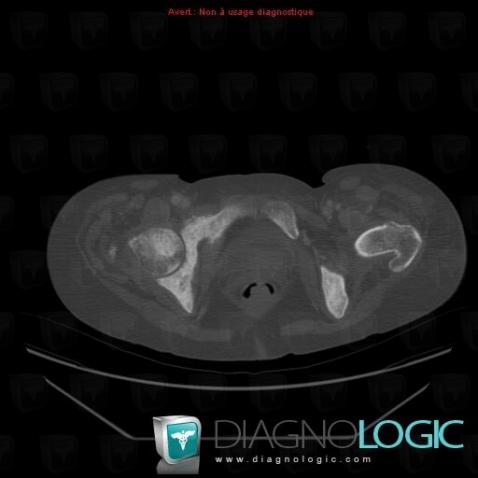

Metastasis, Ilium, CT

Here is the specific information in the key image above:

- Diagnosis Metastasis, Location(s) Ilium, with gamuts Mulltiple osteolysis, Expansive lesion, Ill-defined osteolysis, Spiculated periosteal reaction